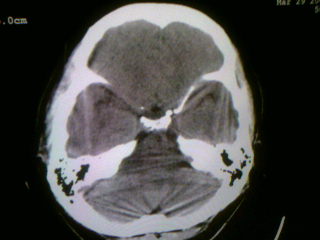

以下是引用wwh40在2009-3-30 17:48:00的发言:[br]右侧基底节区(侧脑室前角旁)可见一三角形低密度影,ct值不详(水样或脂肪密度?),相邻侧脑室较对侧侧脑室前角扩大,[br]意见:1.如果是水样密度,结合上述特点,考虑脑软化灶。[br] 2.如果是脂肪密度,考虑脂肪瘤可能。[br]